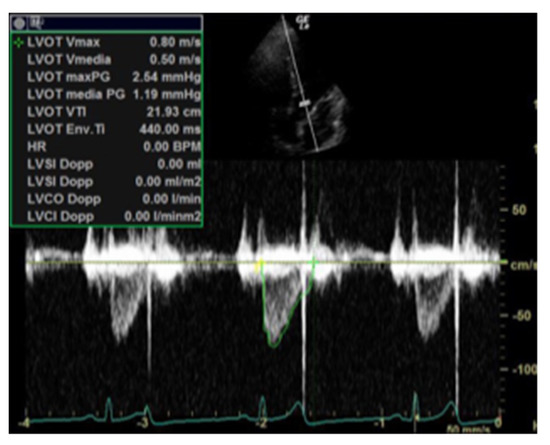

| Perfusion parameters | LVOT VTI and CI | A reliable quantitative parameter that truly reflects circulatory status and global end organ perfusion | LVOT VTI ≥ 18 cm CI ≥ 2.5 L/min/m2 |